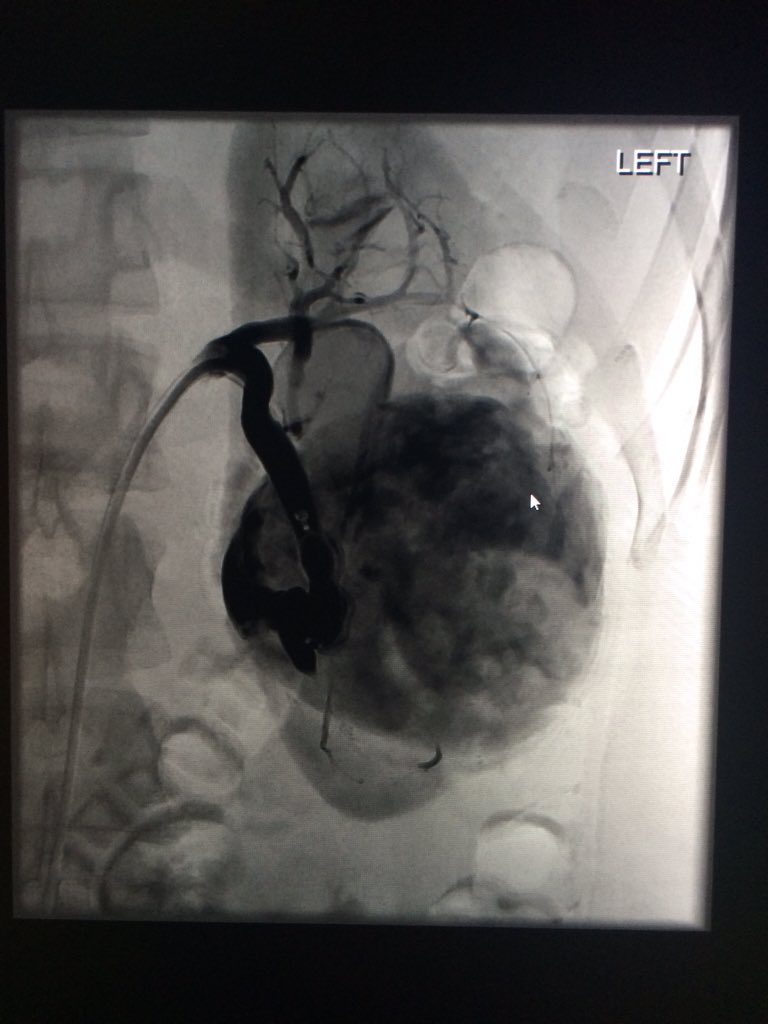

47 yo p/w massive PE s/p systemic tPA and persistent hypotension. Extensive right-sided PE on angio. Thrombus completely removed with FlowTriever mechanical thrombectomy. PA pressure decreased to 30mmHg from 64 mmHg immediately. #IRad @SIRspecialists @SIRRFS @SIR_ECS @JVIRmedia